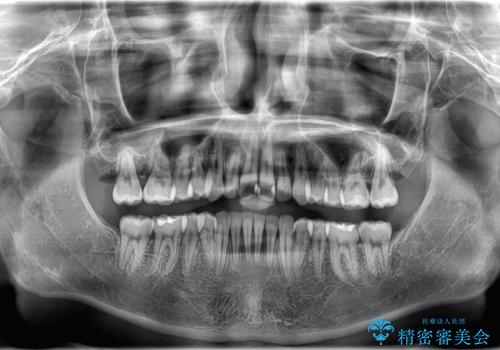

治療途中では咬み合わせの改善を目的としてバイトアップを行い、歯の捻転や叢生を改善しつつ、機能的に安定した咬合を獲得しています。

治療期間は3年2ヵ月と比較的長期となりましたが、見た目の歯並びだけでなく、咬み合わせまでしっかり整えた症例です。

上顎左右4番は90度捻転していたため、改善後歯根露出してしまっているためCTG(歯肉移植)を行う予定です。